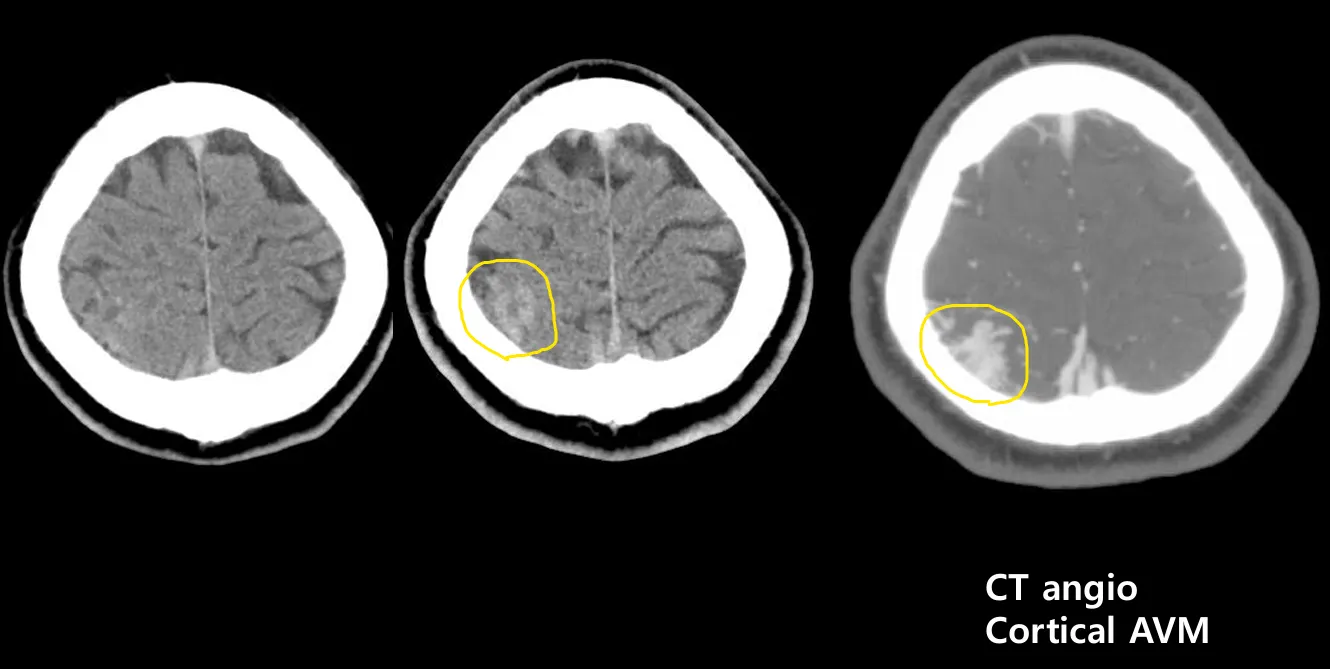

두통환자의 CT마지막 컷 즈음에 우측 뇌에 출혈 비슷한 병변이 나타났고,

이어 촬영한 angio 사진에서 Cortical AV malformation이 발견되었다.